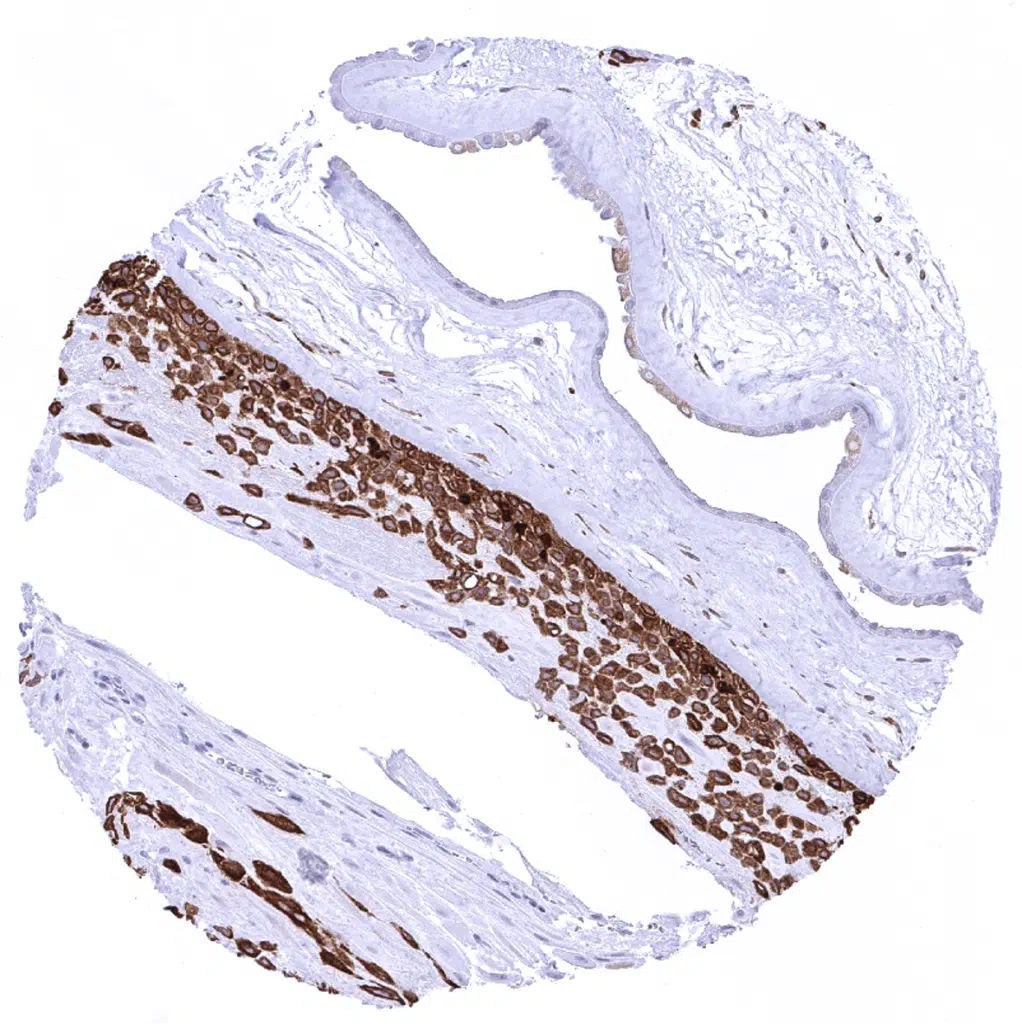

Breast - Luminal cells but not myoepithelial cells stain Cytokeratin 18 positive in normal breast.